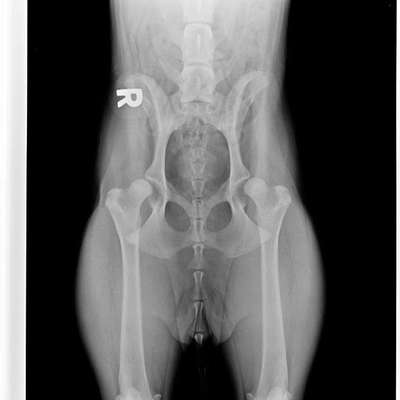

Hallo🙋🏻‍♀️ Wir haben im Mai einen Welpen aus Rumänien adoptiert. Sie war immer schon sehr hüpfend beim laufen und sehr gelenkig. Nun hatte sie vor einem Monat Schmerzen nach kurzem toben, weshalb wir gleich zum Arzt sind. Es gab Schmerzmittel und wir sollten das weiter beobachten. Als es wieder kam, sind wir direkt wieder zum Arzt und haben für letzte Woche einen Termin zum röntgen bekommen. Diagnose: Schwere HD. Unsere Ärztin hat uns Zusätze und Physio empfohlen und gab uns Hoffnung, dass das vllt wieder werden könnte, da sie erst ca.10 Monate alt ist. Hab hier jemanden Erfahrung damit? Tipps? Wir wohnen in der Nähe von Bielefeld und überlegen ob wir uns in einer Klinik bezüglich einer Operation beraten lassen sollten, da wären wir über Erfahrungen ebenfalls sehr dankbar 🙏🏻 Wichtig wäre, dass wir eine OP auf Raten zahlen können!

Das sieht im Röntgenbild echt übel aus.

Unser Labbi Benny hat auch HD, ein kleines bisschen weniger schlimm als Ylvie.